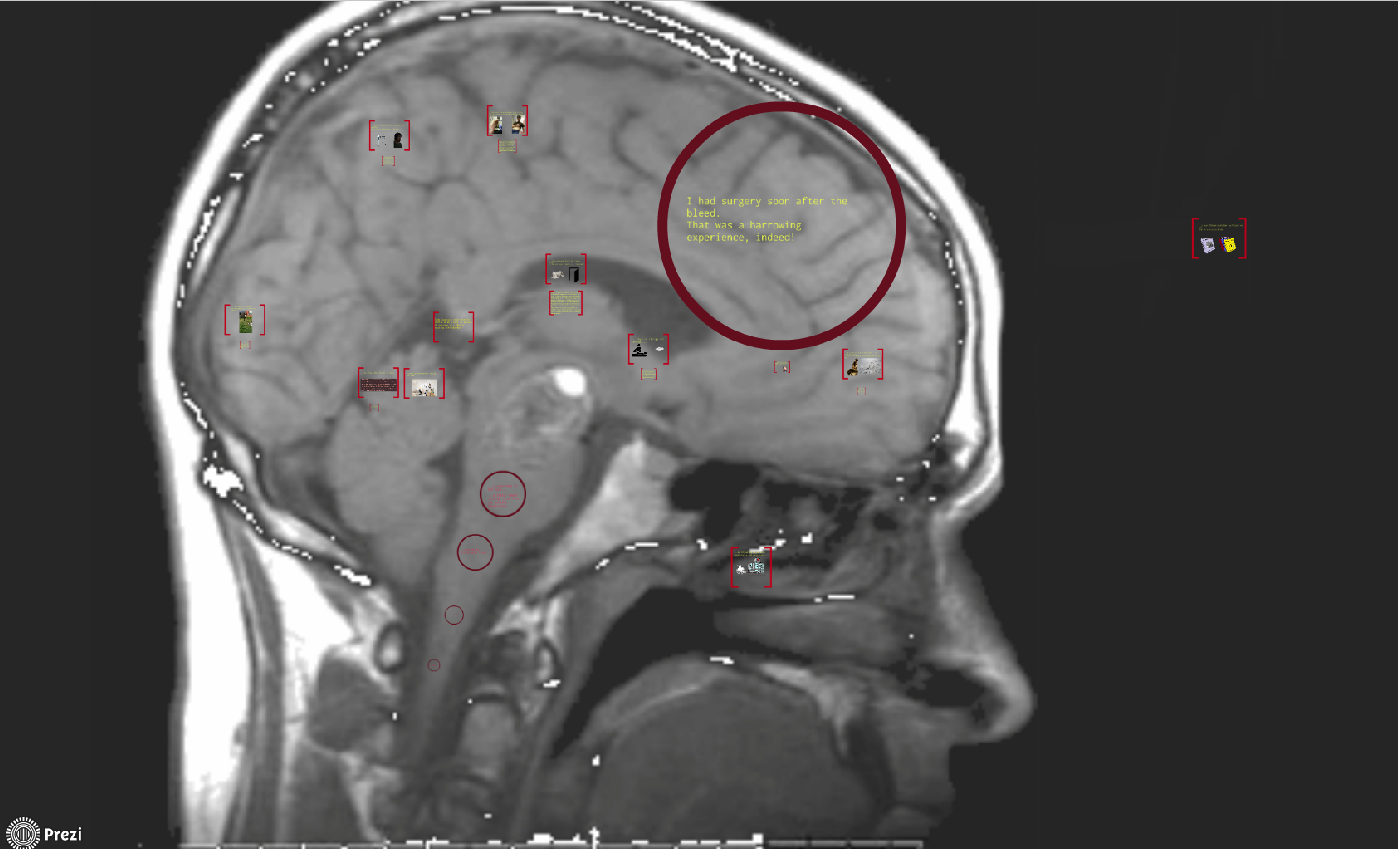

The prezi found here: https://prezi.com/0mvptvuqyviu/ is a synopsis, in a way, of a book I’ve been writing about my experience with a brain injury. It contains excerpts from the book, but guides the viewer with a whimsical poem. I’m gonna go ahead and blame my Ahab like compulsion to write this book for my absence from blogging of late. I made this to show agents and such at a writer’s conference. I was hoping I had enough to get the ball rolling. Turns out, I’m less than halfway done. But, as Ahab got the whale so shall I finish this book – hopefully, it doesn’t do me in, though.